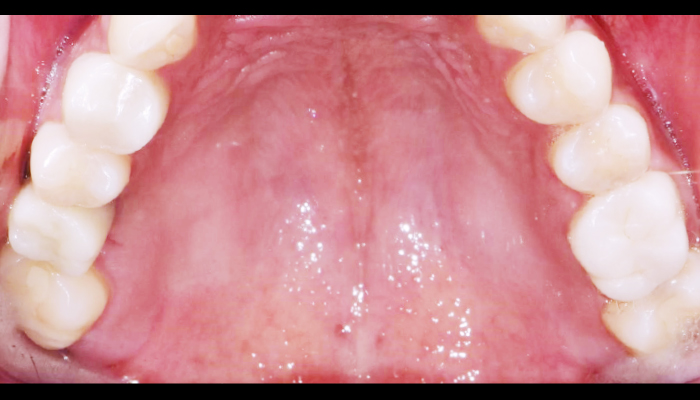

턱관절 증상

주로 입을 벌리거나 저작시 턱관절 부분과 턱, 귀 부위에 통증 또는 소리 발생, 개구 장애, 턱관절 탈구 등이 있습니다.

바른훈치과만의 특별한 턱관절 치료방법

• 악습관 및 자세교정

• 물리치료(레이저&전기자극요법)

• 장치치료(스플린트)

• 주사치료(보톡스)